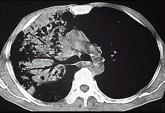

问题 男,30岁,咳嗽咯血,盗汗1个月,伴消瘦无力发热,CT如图,应考虑为 ( )

选项 A.右上肺大叶性肺炎 B.右上肺干酪性肺炎 C.右侧脓胸 D.右上肺多发肺脓肿 E.右上肺不张

答案 B